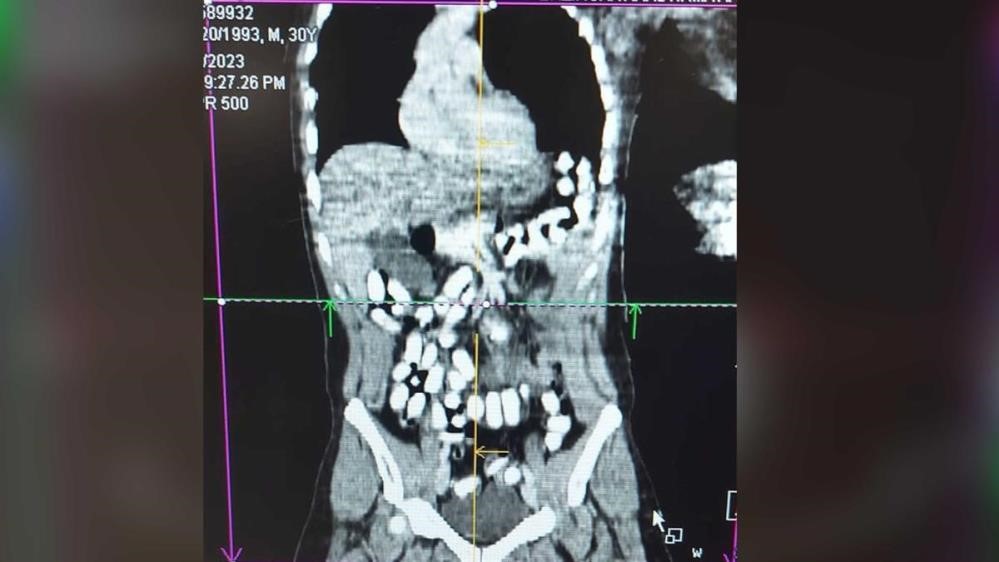

Midesinde uyuşturucu taşıyan şahıs tutuklandı

Erzincan’da midesinde 977,60 gram Afyon sakızı taşıyan şahıs tutuklandı. Erzincan İl Emniyet Müdürlüğü Narkotik Suçlarla Mücadele Şube Müdürlüğü ekiplerince, uyuşturucu ve uyarıcı maddelerin imal ve ticareti veya temini, gerek kullanmak için satın alınması, kabul edilmesi veya bulundurulması, gerekse de kullanımının kolaylaştırılması veya özendirilmesi eylemlerine ilişkin yapılan çalışmalarda; Türk Ceza Kanunu 188’inci maddesi “Uyuşturucu veya uyarıcı madde imal ve ticareti” suçuna ilişkin polis uygulama noktasında durdurulan, bir araçta bulunan A. H. isimli İran uyruklu şüpheli alınan iç beden muayenesi kararına istinaden hekim gözetiminde çekilen tomografi neticesinde mide ve bağırsak kısmında 126 adet kapsül halinde daralı ağırlığı ise 977,60 gr Afyon sakızı ve 25 adet Metadon hap ele geçirildi. Midesinde uyuşturucuyla yakalanan A.H. ise gözaltı işlemlerinin ardından çıkarıldığı mahkemece tutuklanarak cezaevine gönderildi.